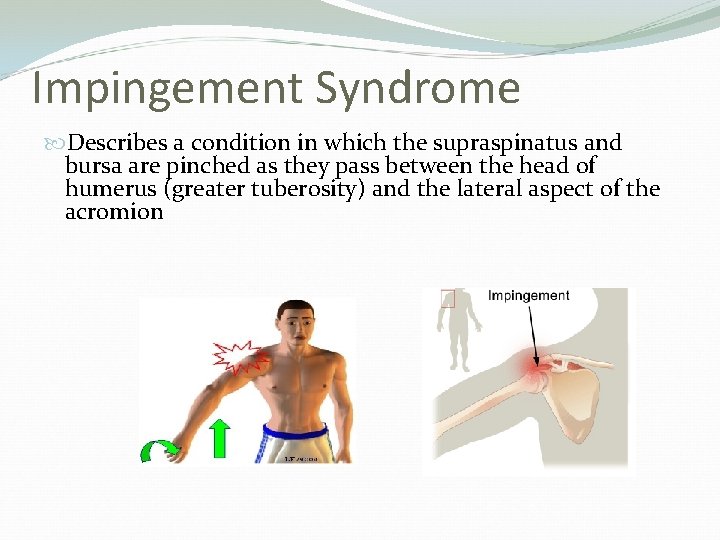

Impingement Syndrome Describes a condition in which the supraspinatus and bursa are pinched as they pass between the head of humerus (greater tuberosity) and the lateral aspect of the acromion